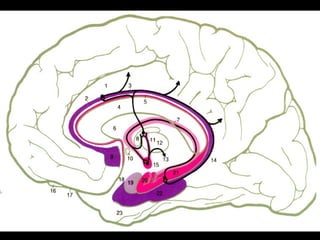

CIRCULAÇÃO LIQUÓRICA

• O LCR circula nos ventrículos laterais,

no canal central da medula e nos espaços

sub aracnóideos.

• Atua como um liquido tampão que distribui

e absorve forças externas ou internas que

poderiam lesar o cérebro e a medula.

• Regulação na variação de volume na

produção e na absorção.

Anatomia cerebral

• O LCR desempenha a função do sistema linfático

nos outros tecidos ( SNC não tem linfa )

• Transfere substância do sangue para os

tecidos nervosos ( BHE )

• A troca de eletrólitos é mais fácil nos

ventrículos que nos espaços sub aracnoideos.

• A troca de água é mais rápida nas cisternas

que nos ventrículos.

• Formação do LCR        plexos coróides ,

• Pode-se ter pequena produção do LCR,

nos espaços sub aracnoideos e peri vascular.

• Formação , circulação e absorção contínua.

( 120 a 150 ml - volume total )

• Produção diária de 400 a 500 ml

( troca a cada 6 a 7 horas ).

•   Os plexos coróides são franjas de

grupos capilares de pia máter que

invaginam em delicadas paredes

ependimárias dos ventrículos.

• Os maiores PC estão nos ventrículos laterais

( produzem + LCR ) .

• Pressão do LCR 70 a 120 mmH2O.

• O LCR é reabsorvido para o sangue através

das granulações aracnoídeas e através das

paredes dos capilares do SNC e pia máter.

• Pequena quantidade de LCR contidos nas

bainhas dos nervos cranianos e espinhais

podem ser reabsorvidos para

vasos linfáticos extra durais.

• Pressão liquórica pode haver reabsorção

pelo plexo coróide.